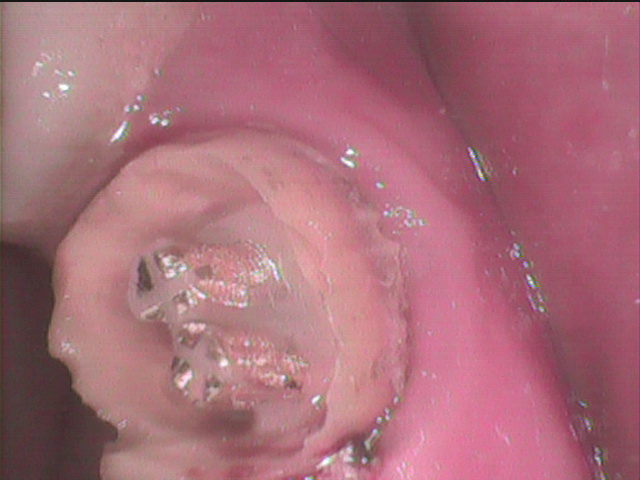

修復物の除去開始 ええ!ジルコニアではありません。

よくあるパターンですが、これはレジンクラウンでした。

嫌なものが見えてきました。

スクリューピンが2本

周囲のレジンをゆっくり落としてゆきます。

実態が見えてきました。

2本がくっついていると

除去しにくい。

もしも除去中に歯根が割れたら

終わりです。